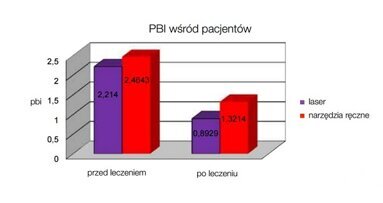

Zapalenie przyzębia prowadzi zwykle do destrukcji tkanek otaczających ząb. W praktyce stomatologicznej zastosowanie technik laserowych zyskuje na ...

Zapalenie przyzębia prowadzi zwykle do destrukcji tkanek otaczających ząb. W praktyce stomatologicznej zastosowanie technik laserowych zyskuje na ...

Higiena przyzębia jest integralną częścią skutecznej terapii periodontologicznej (Axelsson & Lindhe, 1981). Jej celem jest ustabilizowanie ...

Zapalenie przyzębia oznacza zniszczenie więzadła ozębnowego oraz podparcia kostnego na skutek działania stanu zapalnego. Przebieg tej choroby ...

Zapalenie przyzębia oznacza zniszczenie więzadła ozębnowego oraz podparcia kostnego na skutek działania stanu zapalnego. Przebieg tej choroby ...